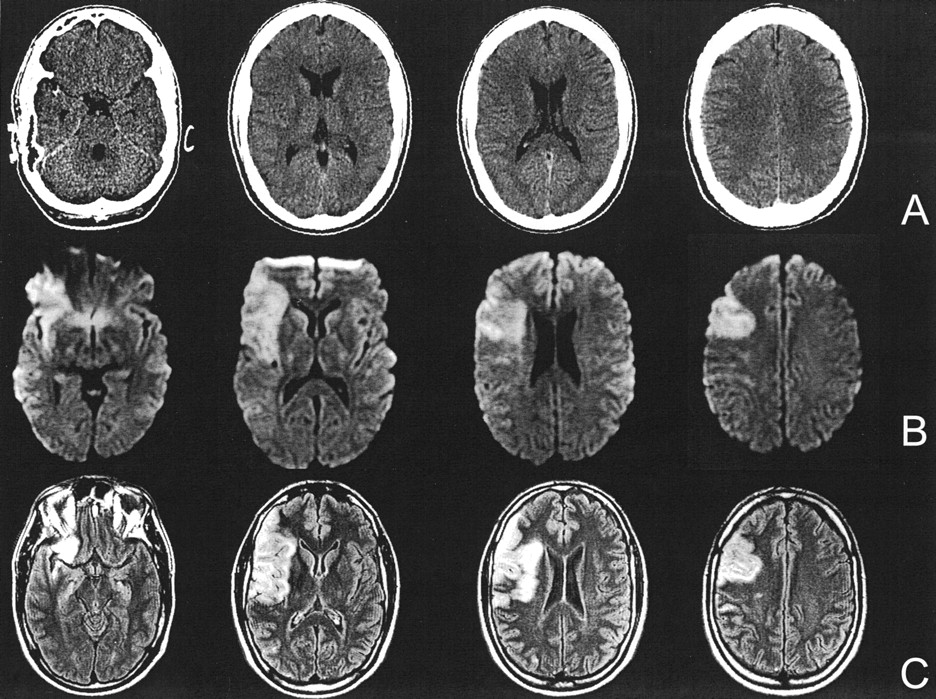

Case of a 62-year-old patient with aphasia and right hemiparesis. (A) CT scans obtained 100 minutes after symptom onset, (B) DW images obtained 120 minutes after symptom onset, and (C) follow-up FLAIR images. DW images were rated positive by all raters and show hyperintensity in the left MCA territory. CT scans were rated normal by five of the six raters. With the knowledge of the DW images, there might be a subtle hypoattenuation in the left insular ribbon region on CT scans. However, the follow-up FLAIR images reveal only small ischemic leasons of the left insular ribbon and parietal regions, with normalization of large parts of the former diffusion-restricted area.